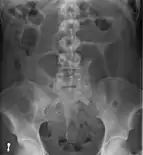

Plain X ray of a cecal volvulus Plain X ray of a cecal volvulus

CT scan of a cecal volvulus CT scan of a cecal volvulus